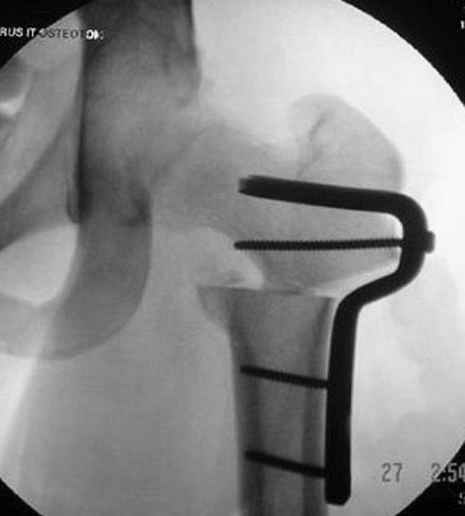

7:30 начало операции, больной на спине, попытка репозиции после анестезии N3, укладка больного на боку, доступ Kocher- Langenbeck, состояние седалищнего нерва около 2.5см кровоподтек, через joistick головка бедра приподнята, освобовождение сустава, фрагмент заднего края более 3х4 см репонирован на свое место. После промывания

сустава, репозиция вывиха (N4), фиксация фрагмента 2.7(4) мм шурупами и допольнительно реконструктивной пластиной на 8 дырок, фиксация 3.5мм шурупами проксимально и дистально.

Интраоперционные N5 косая запирательная и N6 подвздошный снимок

11:50 больной в послеоперационной, рентгенограмма N7, компьютерная томограмма в тот же день N8-10